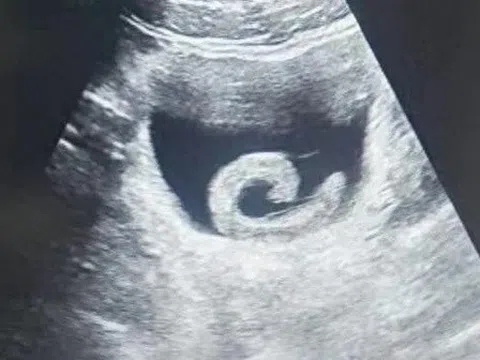

Chiếc máy trăm tỷ đồng ở bệnh viện phụ sản lớn nhất TP.HCM

06:00 31/10/2025

Bệnh viện Từ Dũ đưa vào hoạt động khu chẩn đoán hình ảnh hiện đại, đầu tư hàng trăm tỷ đồng với hệ thống...